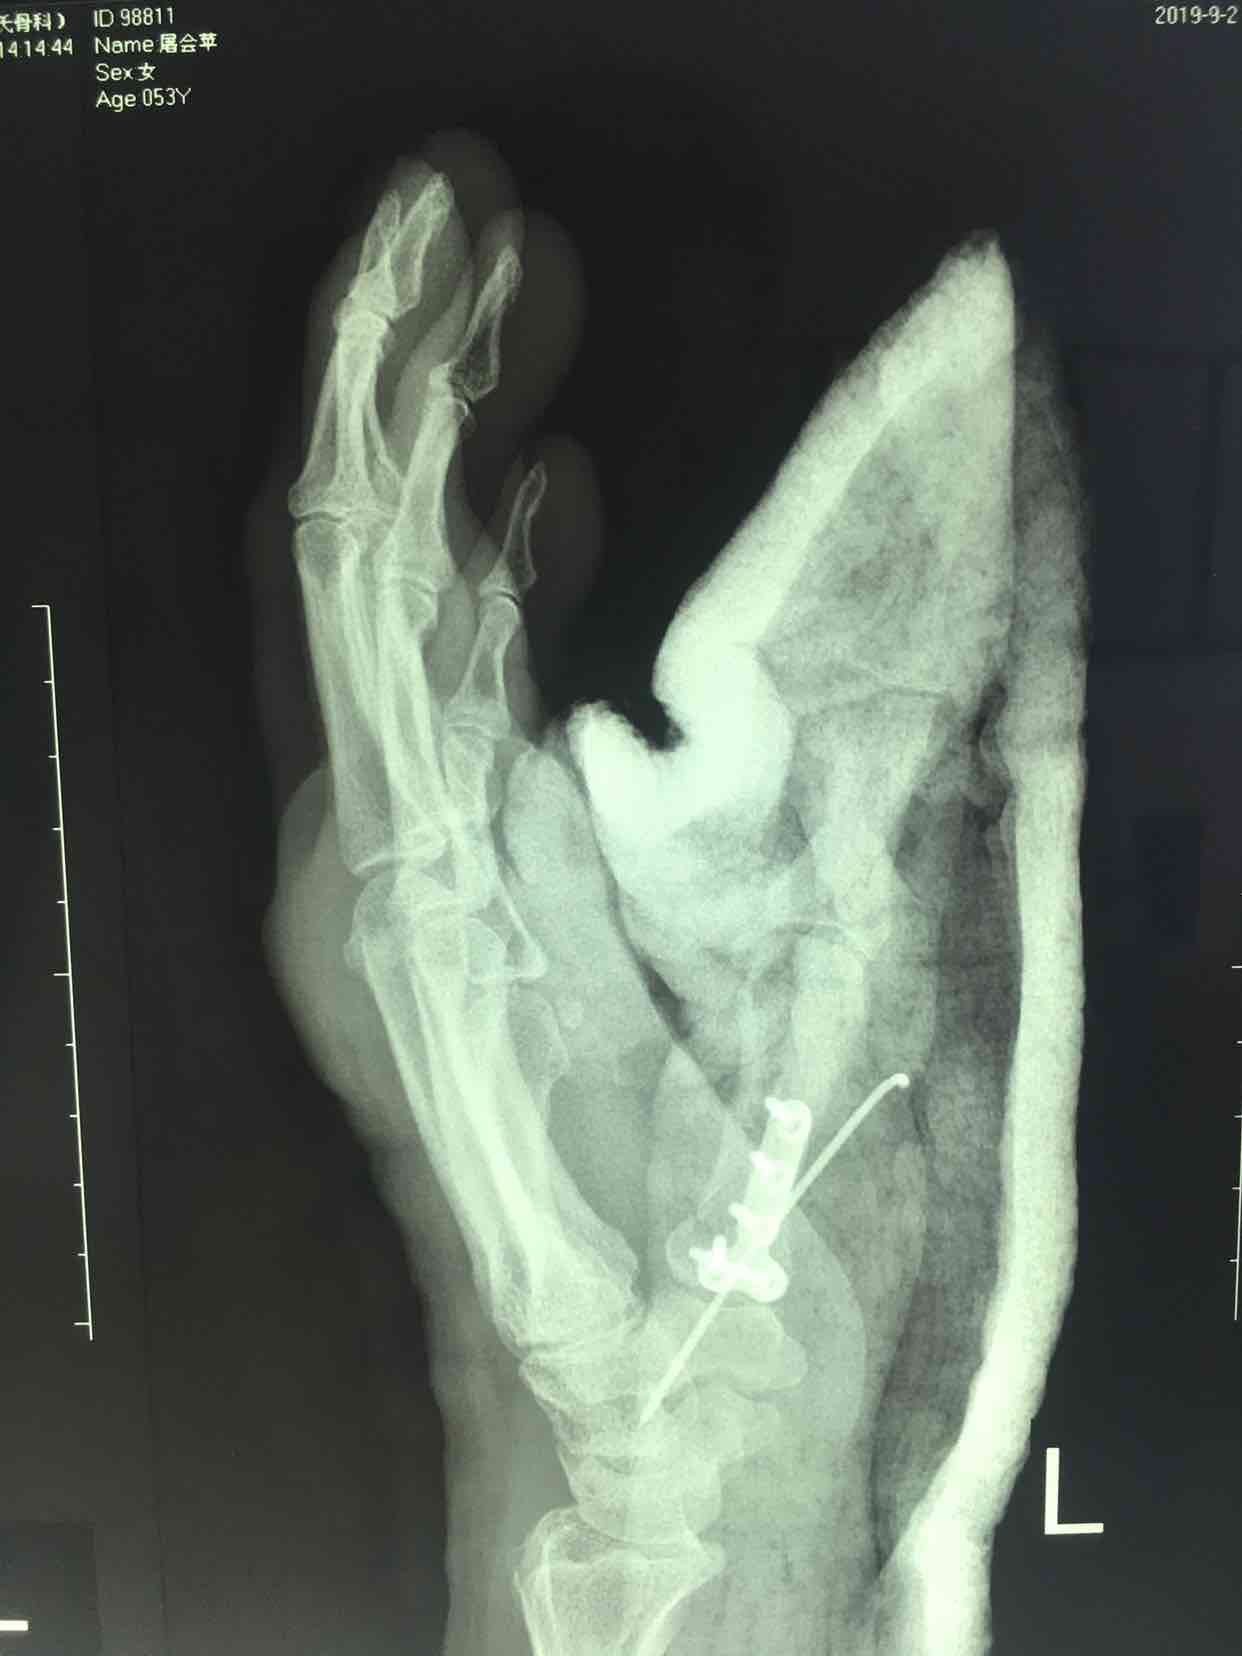

第一掌骨基底部骨折(微钢板固定)

诊断左手第一掌骨基底部骨折在臂丛麻醉下行切复内固定术,术后抗炎消肿等处理,石膏托外固定。